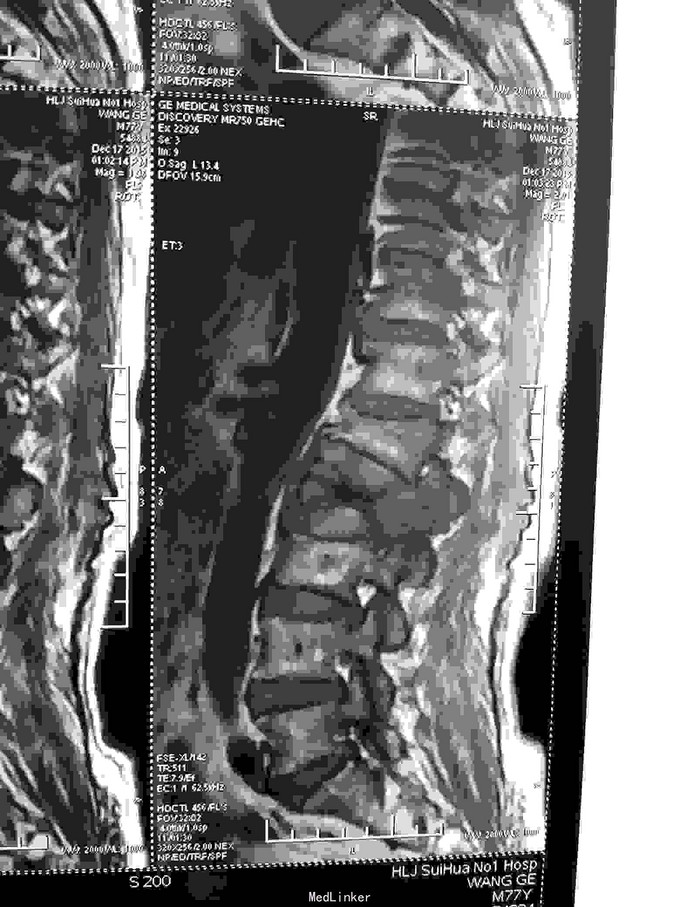

患者老年男性,77岁。因:腰痛,伴双下肢放射痛。活动受限二天。来诊。病人近半年间断腰痛,休息减轻。劳累加重。近二日腰背部疼痛明显加重。不能平卧于床。行走困难。双下肢放射痛。急来诊。因不能平卧,无法查核磁共振,门诊以:腰间盘突出收入院。

查体:神志清,语言流利。呼吸平稳。腹软,腰背部外形较好,无畸形。不能平卧,屈伸活动受限。床上取侧身蜷腿弯腰卧位。双侧下肢放射痛。肌力减退。皮肤感觉麻木。无辅助检查。

根据病史查体诊断:腰间盘突出症待确诊。应用消肿营养神经镇痛治疗。一天。查核磁共振示:腰椎多节段间盘突出伴椎管狭窄。第二腰椎骨破坏侵及椎板。部分突入椎管,脊髓受压。诊断:腰间盘突出伴椎管狭窄。第二腰椎转移癌,脊髓受压。经与家属沟通,查双肺CT:双肺下叶炎症。肺部纤维化。可见肿瘤阴影。肋骨及胸膜受累。胸椎部分骨破坏。最终诊断:双肺癌,胸椎,腰椎骨转移,脊髓受压。多节段腰椎间盘突出。病人至肿瘤科治疗。